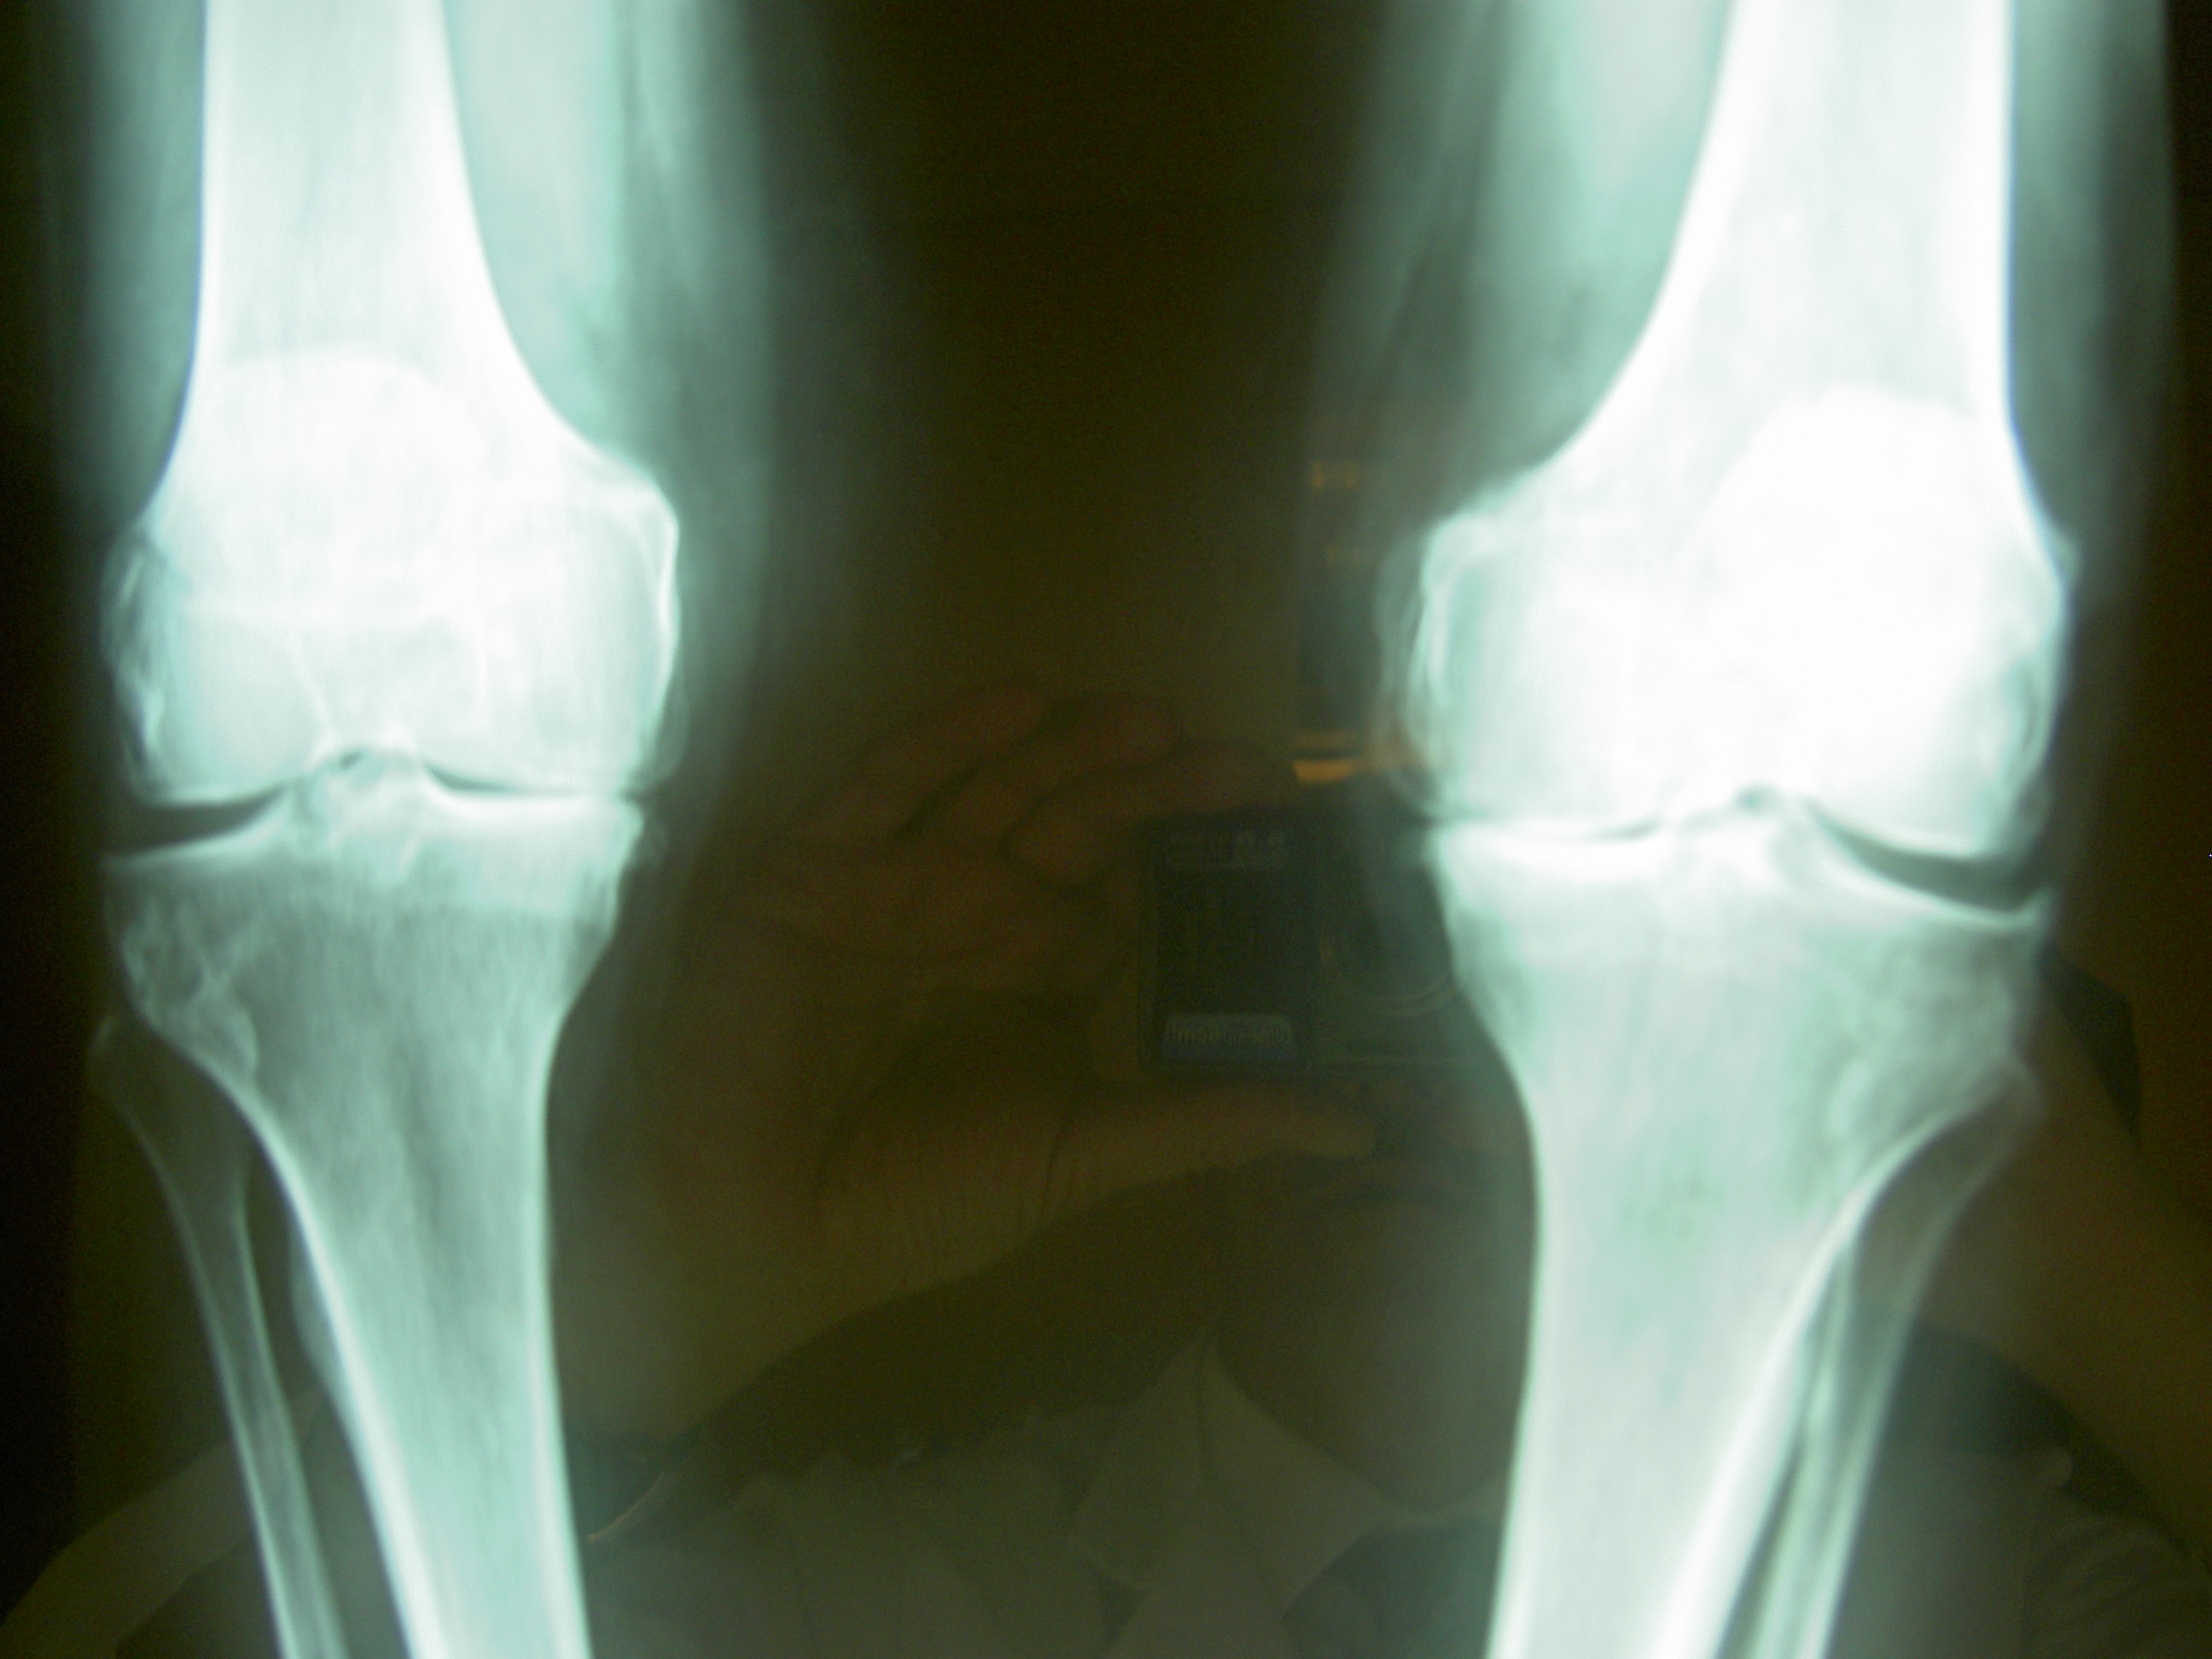

El dolor en ambas rodillas y sus problemas funcionales

Personas con dolor en ambas rodillas, en comparación con aquellos con dolor en una sola rodilla, tienen más problemas para una recuperación total, de acuerdo en  un informe del 26 de febrero en atención e investigación de la artritis.

Los hallazgos indican que los pacientes con dolor unilateral, probablemente tendrán el doble de dificultades para un  buen funcionamiento físico despues de recuperarse. Además, en los sujetos con dolor bilateral aumentaron las probabilidades de desarrollar deterioro de la función en un 30%.

"Nuestro principal conclusión fue que las personas que tenían dolor en ambas rodillas eran más propensos a desarrollar un bajo nivel de funcionamiento y tenían menos probabilidades de recuperarse de un bajo nivel de funcionamiento con el tiempo, en comparación con las personas con una sola rodilla dolorosa".